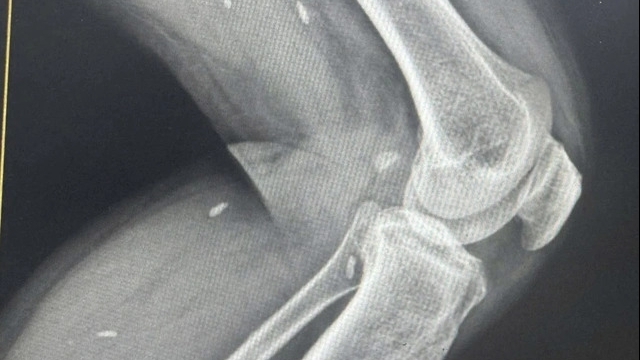

| Dùng thuốc cam đánh tưa lưỡi khiến trẻ bị nhiễm độc chì trong máu |

Kết quả xét nghiệm của bệnh nhi cho chỉ số men gan tăng cao, lượng chì trong máu: 226.5 µg/dl cao gấp nhiều lần mức cho phép. Qua kết quả cận lâm sàng bác sĩ chẩn đoán bệnh nhi bị nhiễm chì trong máu nặng.